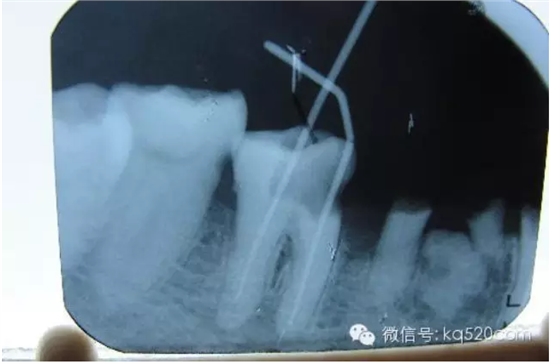

前面我們講過,牙齒內(nèi)部實際上是一個空腔,這個空腔我們稱之為“根管系統(tǒng)”。同單純的“爛神經(jīng)”相比,“根管治療”不僅僅是要將“根管”中的牙髓“殺死”,還要將牙髓從“根管”中清除出來,然后要進行徹底清理和嚴格消毒,并用人工的充填材料將“根管”嚴密填塞。這就是所謂的“根管治療”。一個“根管治療”做得是否完善,會在很大程度上決定了這顆牙齒的壽命。而且,不僅僅是對于牙髓炎,牙齒的其他疾病(如根尖周炎等)也需要采用根管治療的方法才能得到治愈。從傳統(tǒng)的根管治療三部曲(即根管預備、根管消毒和根管充填)來講,一般的根管治療需要三次。但是這僅僅是理論上的情況,實際上因患者而異,因牙而異,因醫(yī)生的技術(shù)水平而異。現(xiàn)代根管治療技術(shù)有了飛躍性的發(fā)展,有些根管治療甚至可以一次完成。